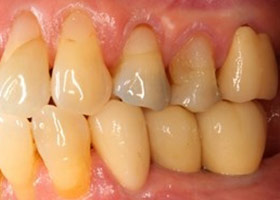

治療前全口x光片、口內照片

術前缺牙無法咀嚼